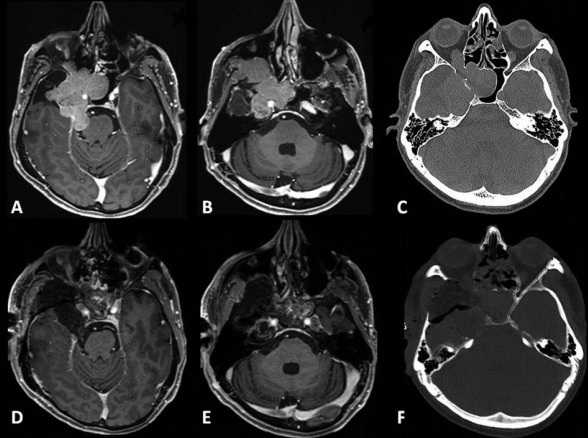

41岁男性,蝶眶脑膜瘤继发眼球突出,并延伸至前床突和蝶窦(SphS)。

图1A-D:术前MR显示蝶眶区脑膜瘤占位,增强病灶,浸润延伸至蝶腭窝(黄色箭头)。

术中操作:Froelich教授经翼点入路开颅,剥离海绵窦侧壁后,行硬膜外前床突切除术。切除硬脑膜内肿瘤及侵袭硬脑膜及眶周的肿瘤。使用颅包膜补片对硬脑膜缺损进行水密封闭后,剥去圆孔(FR),暴露翼腭窝(PPF)。肿瘤沿V2神经鞘播散生长,磨除上颌窦(MaxS)后,打开蝶窦(SphS)。

术后组织病理学:I级脑膜上皮型脑膜瘤。

术后临床情况:眼球突出症状立即好转,术后恢复好,病程平稳。术后V2神经功能包括角膜感觉正常,无干眼、流泪异常等症状,按期拆线出院。

▼术后影像复查:证实肿瘤被完全切除。E-H:术后轴位MR图像显示肿瘤完全切除。